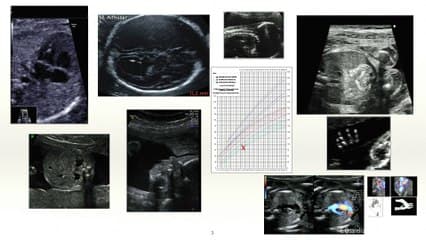

La plus grande ressource vidéo en échographie fœtale de France. Conférences, cours magistraux, démonstrations pratiques et podcasts par les experts du Collège Français d'Échographie Fœtale.

La médiathèque du Collège Français d'Échographie Fœtale (CFEF) constitue l'une des plus importantes collections de ressources vidéo dédiées à l'échographie fœtale en France. Avec plus de 3 261 vidéos, elle couvre l'ensemble des thématiques liées à la pratique échographique prénatale.

Vous y trouverez des conférences présentées lors des congrès nationaux et internationaux, des cours magistraux dispensés par des experts reconnus, des démonstrations pratiques sur des cas cliniques réels, ainsi que des podcasts et tables rondes sur les dernières avancées de la spécialité.